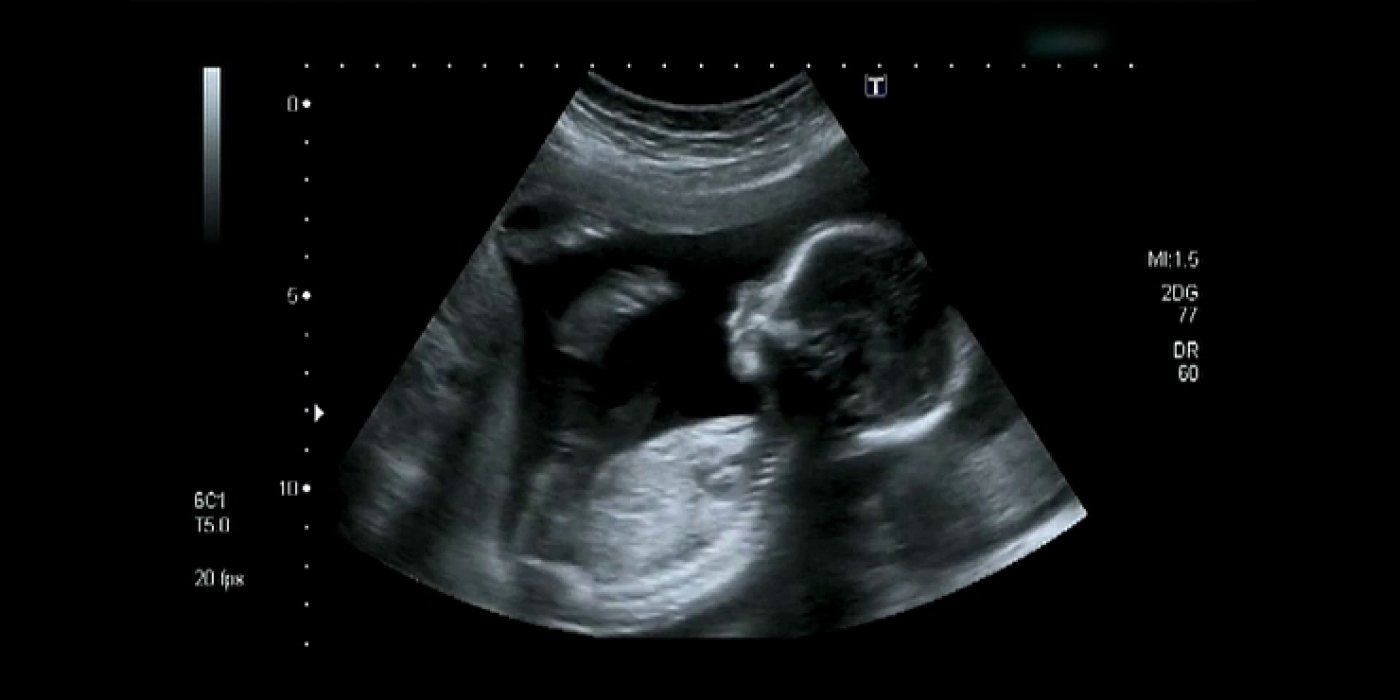

Beba u trbuhu istražuje svoja osjetila, uči papati dok siše palac, razvija svoj okus, sanja, vježba i zabavlja se, svaka na svoj način.

U trbuhu svake trudnice prilično je aktivno a maternica svake buduće majke doista je igralište za bebu. Pa dok one čekaju dolazak svoje bebe, i ona se također priprema za vanjski svijet.

Beba u ovom fascinantnom videu koji ima preko 10 milijuna pregleda, simpatično se odbacuje se nogicama i izgleda kao da vježba u vodi! Savršeno ulovljen trenutak bebinog raspoloženja, pogledajte!